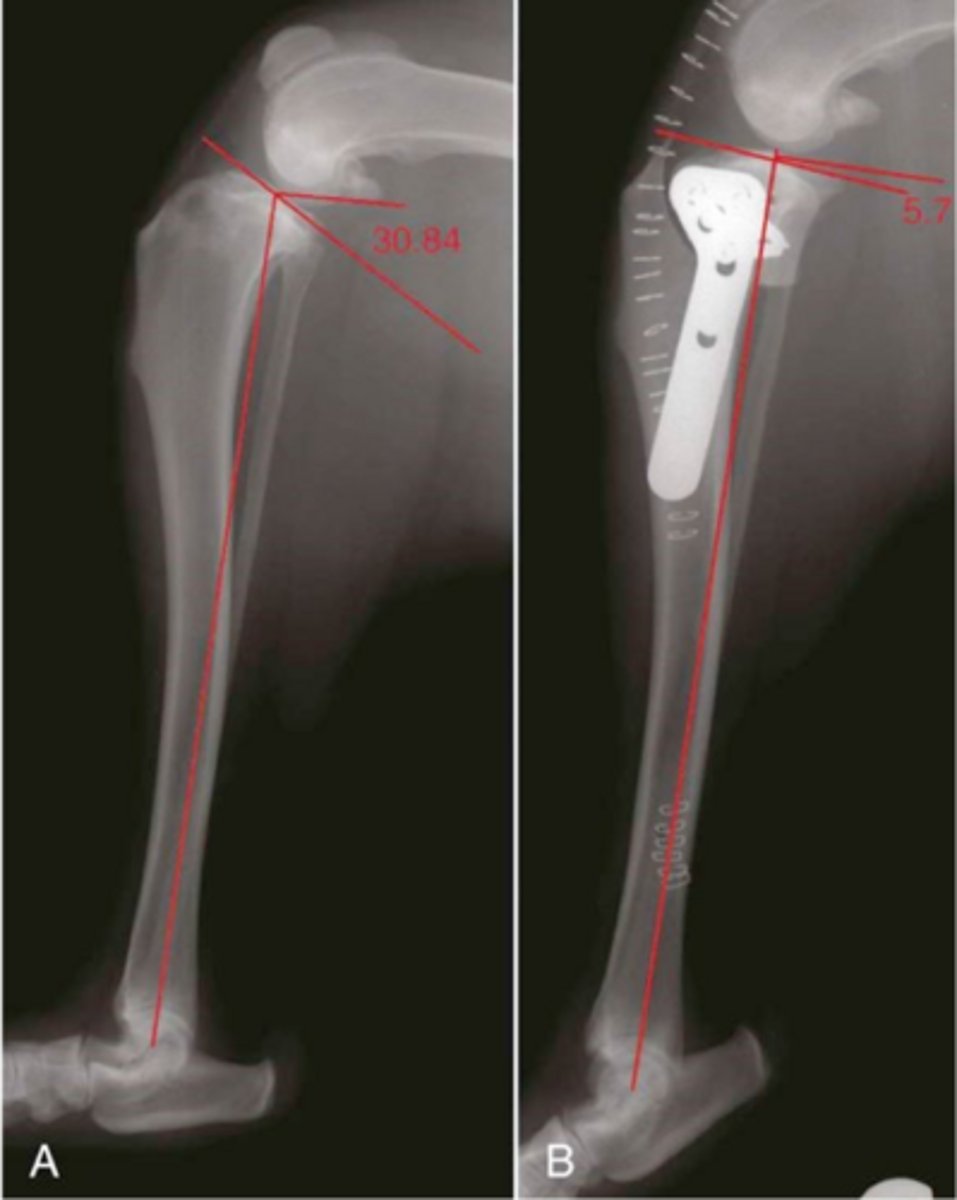

RADs of. TPLO dog to a slope of 5 degrees

what is shown here

1. tibial plateau slope of 5-7 degrees

2. work to control tibial thrust by forcing control to caudal cruciate lig. and active constraints of stifle via quadriceps

what is the intent of the tibial plateau leveling osteotomy (TPLO) sx.